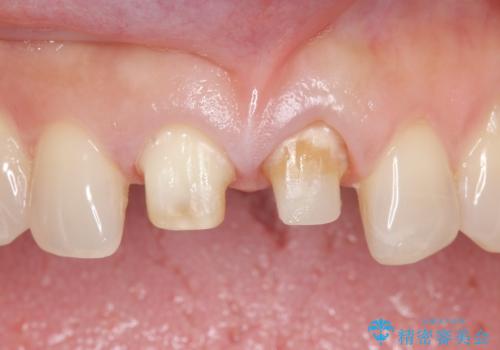

- 前歯の変色が気になるのでセラミックによる治療を行いたいといらっしゃった方の症例です。

左上1番目の歯の再根管治療終了後、左右1番目の2歯をオールセラミッククラウンで補綴しました。